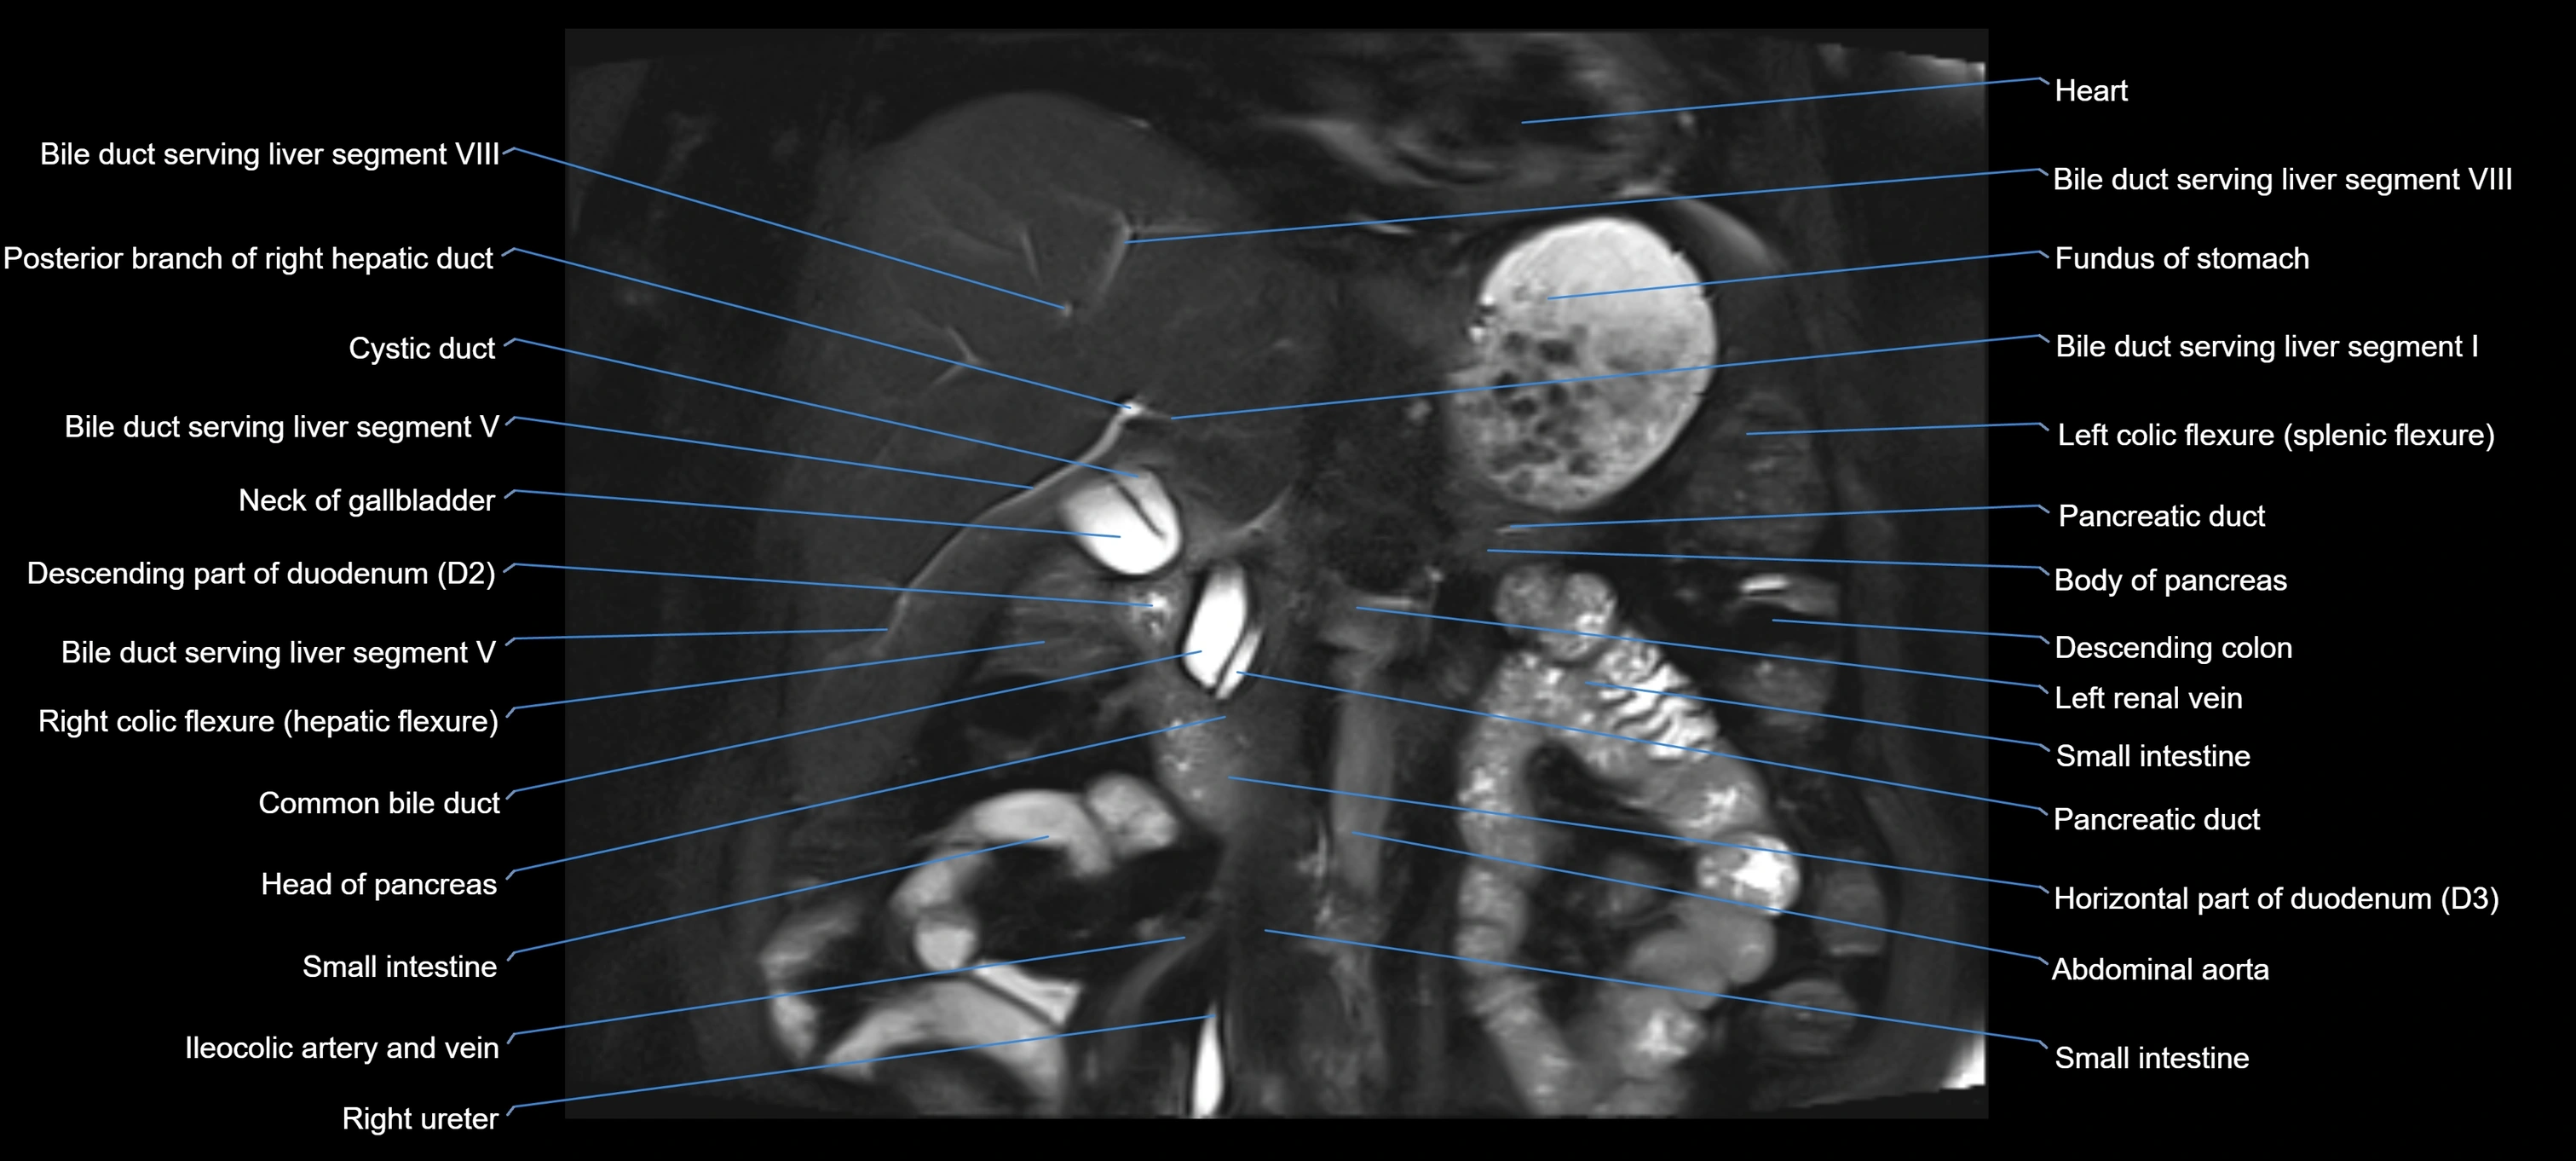

T2 TSE Fat-Saturated 3D (MRCP sequence):

• Duct visualized as a continuous bright tubular structure joining or parallel to the main pancreatic duct

• Allows 3D reconstruction of ductal anatomy and variants

• Excellent for diagnosis of pancreas divisum

Thick-slab T2 Fat-Saturated HASTE:

• Shows the accessory duct as part of the biliary–pancreatic system in a projectional image

• Highlights communication with main pancreatic duct and opening into the minor papilla

• Filling defects (stones, strictures) seen as dark spots within bright fluid